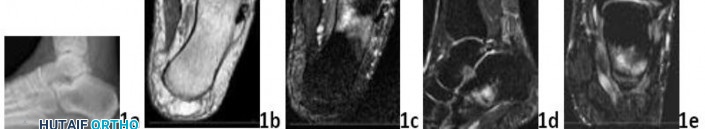

Q 1 1a 1b 1c 1d 1e A 43-year-old female factory worker has had a 6-month history of right plantar and lateral foot pain. She has pain with weight bearing and has difficulty standing at work. Management consisting of physical therapy, time off of work, and fracture boot immobilization has failed to provide relief. She is overweight and, as a result of the pain, cannot exercise to lose weight; thus she is getting worse instead of better. Examination reveals that the foot is not grossly swollen but is diffusely tender over the lateral, plantar, and medial hindfoot. The alignment is normal and the posterior calf muscles are mildly tight. A lateral radiograph is shown in Figure 1a and MRI scans are shown in Figures 1b through 1e. These findings are most consistent with which of the following?

DISCUSSION: The studies are most consistent with a stress fracture or insufficiency fracture of the anterior portion of the calcaneus. The radiograph shows normal findings. There is increased signal involving the inferior anterior aspect of the calcaneus on the T2-weighted images (Figures 1c through 1e), which is consistent with edema. There is also an abnormal trabecular pattern within this region with changes on the T1 and T2 images consistent with a stress or insufficiency fracture of the calcaneus. Whereas there is some increased signal from the os trigonum and the origin of the plantar fascia, these diagnoses are inconsistent with her symptoms. The MRI findings of osteomyelitis (decreased T1 signal and increased T2 signal) with secondary soft-tissue findings of adjacent soft-tissue ulcers, cellulitis, phlegmon, abscess, sinus tracts, or cortical bone destruction are not present. Complex regional pain syndrome has a wide spectrum of findings on MRI and is usually much more diffuse.

The Preferred Response to Question # 1 is 3.